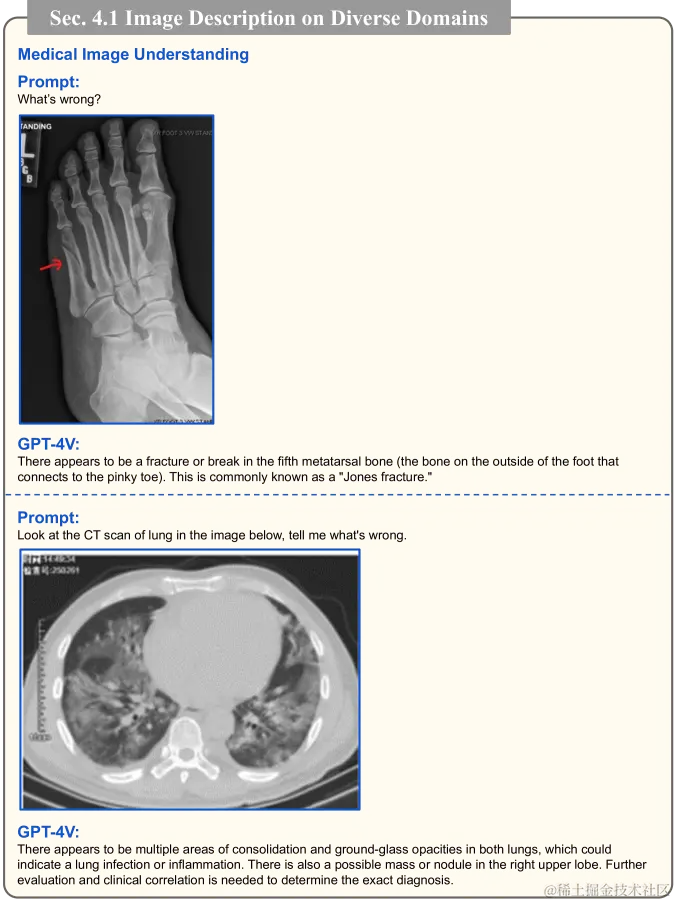

医学图像理解

因患者种群和检测设备的不同,X 射线和 CT 扫描等医学图像经常存在很大的差异。此外,要解读这些图像的视觉内容需有专业知识。在图 18 中,通过给 GPT-4V 提供提示:“描述这个图像”,来测试其性能。结果发现,GPT-4V 能够准确识别 X 射线图上的牙齿和颌骨。当给出提示:“这张 X 射线图上有需要拔除的智齿吗?”时,GPT-4V 能基于视觉上下文进行推理,并解释称,下颌左右两侧的智齿并未完全长出牙龈,可能需要拔除。我们还对其他类型的医学图像进行了测试(如图 19 所示),使用的提示包括:“有什么问题?”和“看看这个 CT 扫描,告诉我有什么问题。”观测结果显示,GPT-4V 能识别 Jones 骨折等常见病症,并能根据肺部 CT 扫描指出可能存在的问题。这些实验显示 GPT-4V 对医学图像有基础的理解能力。更多关于 GPT-4V 在医学领域应用的讨论,请参见 9.3 节。

图 19:医学图像解读成果。GPT-4V 能准确识别如琼斯骨折等常见病症,并根据肺部 CT 扫描结果指出可能存在的问题。更多详细讨论可查看 4.1 节。所展示医学图像均来源于网络。